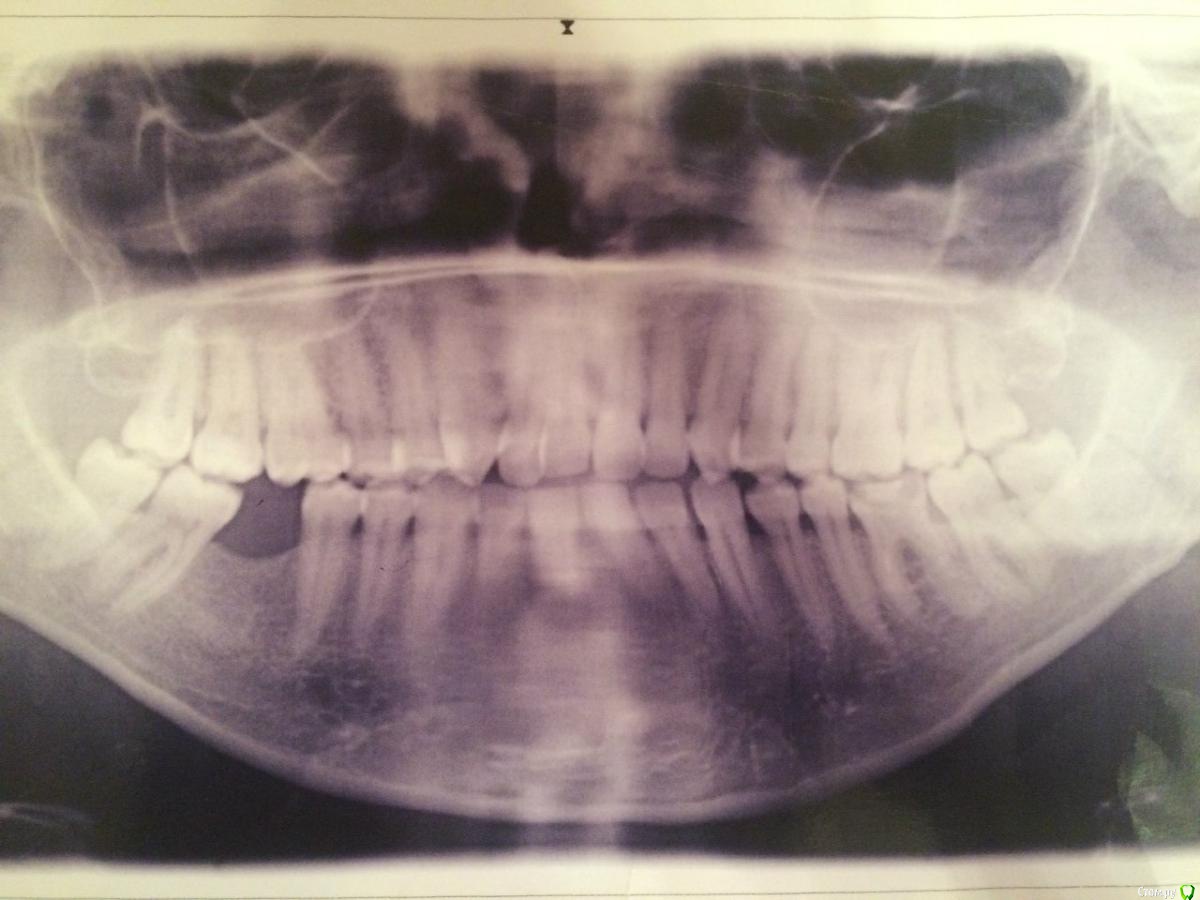

Malinowna Опубликовано 9 января, 2015 Поделиться Опубликовано 9 января, 2015 Добрый день. Очень нуждаюсь в Вашем мнение по поводу брекетов. В наличии дистальный прикус. На данный момент план лечения - удаление четверок на вч. Удаление восьмерок на вч. Возможное удаление восьмерок на нч. Имплантация на место шестерки на нч. Волнует удаление восьмерок, действительно ли это крайняя необходимость? Или они все хорошо расположены и им достаточно места, а для исправления дистального прикуса достаточно удаления 4-к.? К сожалению на руках только один снимок Ссылка на комментарий